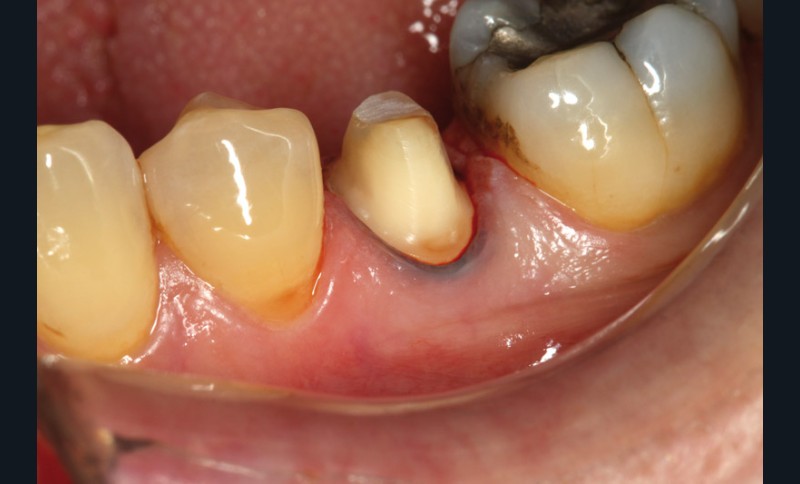

Voici un exemple clinique de mise en œuvre dans le cadre de la réalisation d’une couronne sur une 35, en un seul rendez-vous.

La préparation corono-périphérique est réalisée avec une limite cervicale juxta-gingivale ou légèrement intra-sulculaire, un fil de soie noir est placé dans le sulcus pour améliorer la lisibilité de la limite cervicale.